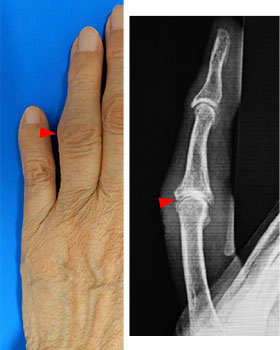

指の中ほどが腫れて曲がる

「ブシャール結節」とは

どんな病気?

ブシャール結節とは

ブシャール結節とは、指の第二関節(PIP関節)で痛みや腫れ、変形などが生じる、変形性関節症の1つです。

ヘバーデン結節と同様に、中高年の女性に多い病気です。

ブシャール結節の主な症状

- 痛み、腫れ

- 熱感

- 変形、太くなる

- 曲がりにくさ、こわばり

- 痛みが引いてからも変形が残る